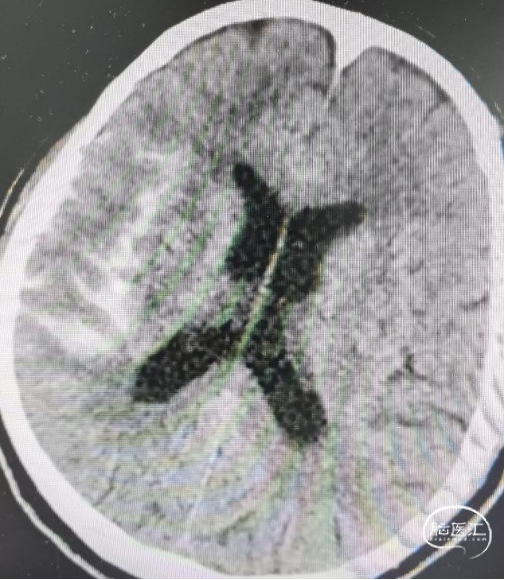

最后全释放支架,序贯撤出微导管,造影可见支架打开完全、贴壁完美,载瘤动脉角度变化小,管腔通畅,动脉瘤Raymond 1级栓塞。

术后情况

术后即刻给予波立维300mg,第二天口服波立维75mg+拜阿司匹林100mg。术后给予低分子肝素抗凝2天,恢复良好,1周后出院,尚未造影复查。